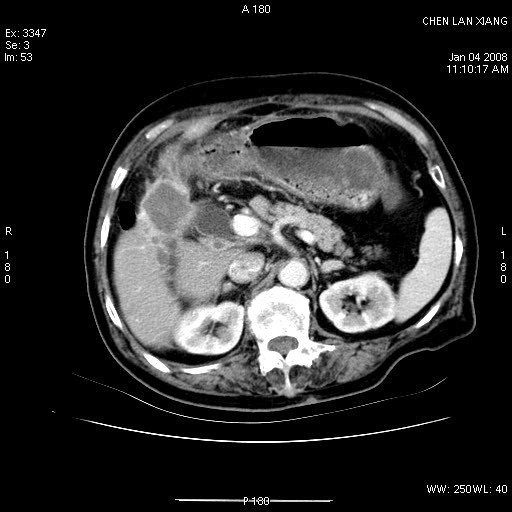

女,76岁,腹痛3-4天,b超示:肝内实性肿物,胆囊强回声,胆总管扩张.

考虑:1、胆总管下端结石伴梗阻性肝内外胆管扩张(肝左叶外侧段肝内胆管多发结石、胆管炎);

2、肿囊癌累及肝,不除外 黄色肉芽肿性胆囊炎。

1 胆总管末端结石伴肝内胆管结石,肝内外胆管扩张。2 胆囊扩大,胆囊壁不规则增厚,内见软组织密度影。考虑:慢性胆囊炎,不除外胆囊癌!

ct所见:1、 肝内胆管结石,肝内外胆管扩张。低位胆道梗阻,胆总管下端结石;2 胆囊扩大,胆囊壁不规则增厚

考虑:胆总管下端结石并肝内外胆管扩张,肝内胆管结石;

标题: 肝右叶病灶

胆囊癌侵犯肝右叶?

1)胆囊癌伴肝脏转移。2)胆总管下端结石、肝内胆管结石伴肝内外胆管扩张。